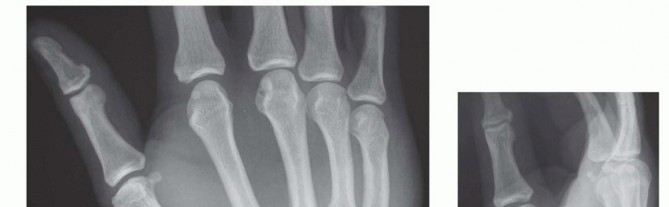

Operative Treatment of Finger Carpometacarpal Joint Fracture-Dislocations